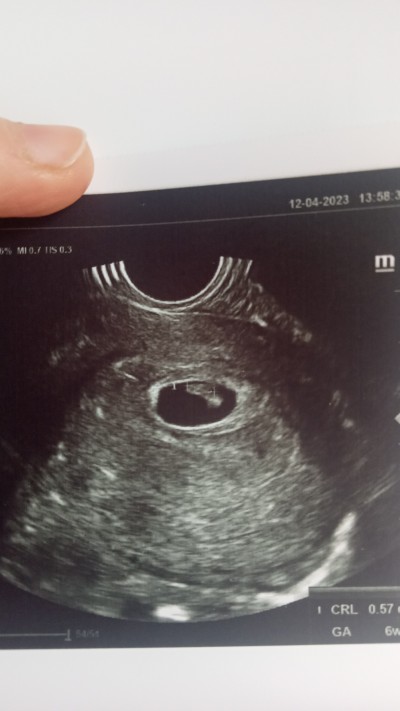

Dün gece baya bı kanamam oldu. Hemen hastaneye gittim. Düşük önleyici iğne vuruldu. Kanamam da kesildi. Bugün doktoruma çıktım. Kanama olması için bir sebep görünmüyor dedi. Ama yine de düşük olmaması için ilaç verdi. 6+3 şuanda kalp atışını da duyduk çok şükür

Gebelik haftası 6